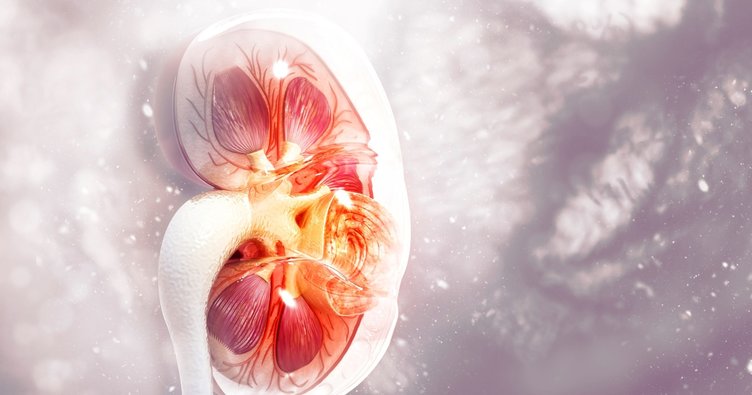

Böbrekler, karnımızda yer alan bir çift organdır. Böbrek idrar yoluna ait bir organdır. Kandaki atık maddeleri ve fazla suyu süzerek idrar meydana getirirler.İdrar, böbrek içerisinde böbrek pelvisi adı verilen bir boşlukta toplanır. Bu boşluk böbreğin orta kısmında yer alır. İdrar böbrek pelvisinden mesaneye doğru üreter adı verilen kanal vasıtasıyla aktarılır. Mesanede biriktirilen idrar daha sonra üretra adı verilen kanal vasıtasıyla vücut dışına aktarılır. Böbrekler ayrıca kan basıncını kontrol eden maddelerin üretiminde bulunurlar. Yine kırmızı kan hücrelerinin üretimine yardımcı olurlar. Böbreklerin üst kısmında böbrek üstü bezi (adrenal bezi) bulunur. Böbreklerin üst kısmı kalın bir yağ tabakası ile kaplıdır. Bu yağ tabakasının dışında da fibroz dokudan oluşan böbrek kapsülü bulunur.

Sağ böbrek üst tarafta ufak tümör,opak ilacı tutmuş ve boyanmış